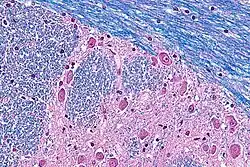

In pure LFB stains, myelin fibers appear blue, with areas of the highest concentration of myelin appearing darker. The blue stain appears on a white background.

Typically, cresyl violet is used as counterstain. Cresyl violet binds to Nissl substance, which is concentrated around a neural cell's nucleus; such a counterstain allows differentiation between myelenated axons, cell bodies, and unmyelenated axons or glial cells. In such a stain, myelin fibers appear blue, neuropil appears pink (or faint purple), and neuron cell bodies appear purple.